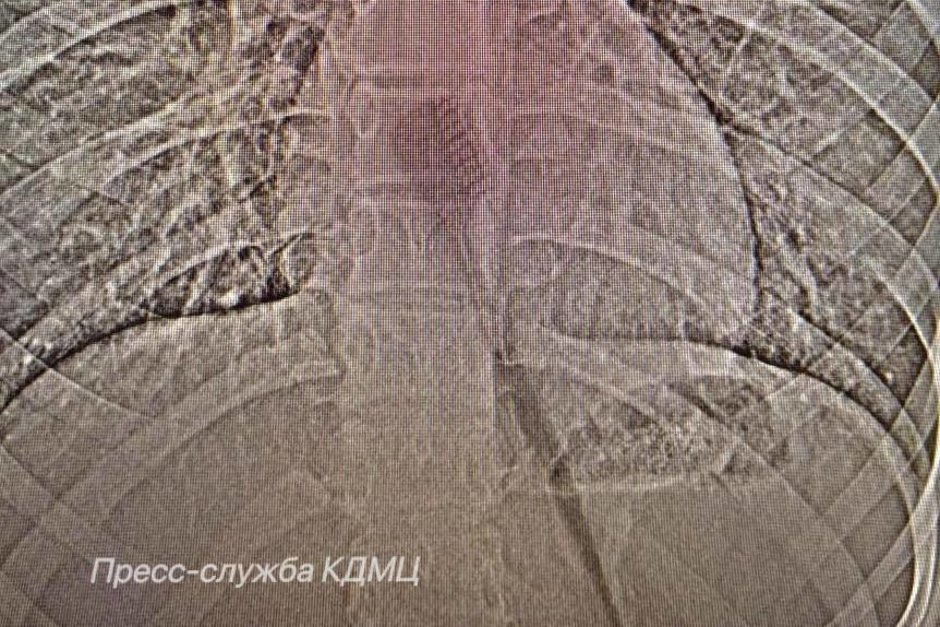

В Набережных Челнах врачи клинико-диагностического медицинского центра (КДМЦ) извлекли из желудка 13-летней девочки 19-сантиметровую зубную щетку, которую она случайно проглотила во время утренней чистки зубов. Медики пояснили, что щетка находилась в желудке и частично в пищеводе, создавая риск повреждения этих органов.

Девочке провели эндоскопическую операцию.